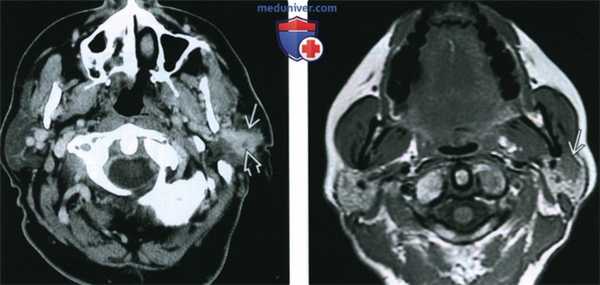

(Слева) КТ с КУ, аксиальная проекция. В левой околоушной железе определяется новообразование с нечеткими контурами, накапливающее контрастное вещество. В центре имеется кистозный участок. Такая картина характерна для мукоэпидермоидного рака промежуточной степени злокачественности.

(Справа) МРТ Т1ВИ, аксиальная проекция. В поверхностной доле околоушной железы имеется образование с четкими контурами и сигналом промежуточной интенсивности. Каких-то характерных признаков, которые позволили бы нам поставить диагноз мукоэпидермоидного рака низкой степени злокачественности, не обнаруживается. Практически при любой опухоли околоушной железы для постановки окончательного диагноза необходима биопсия.